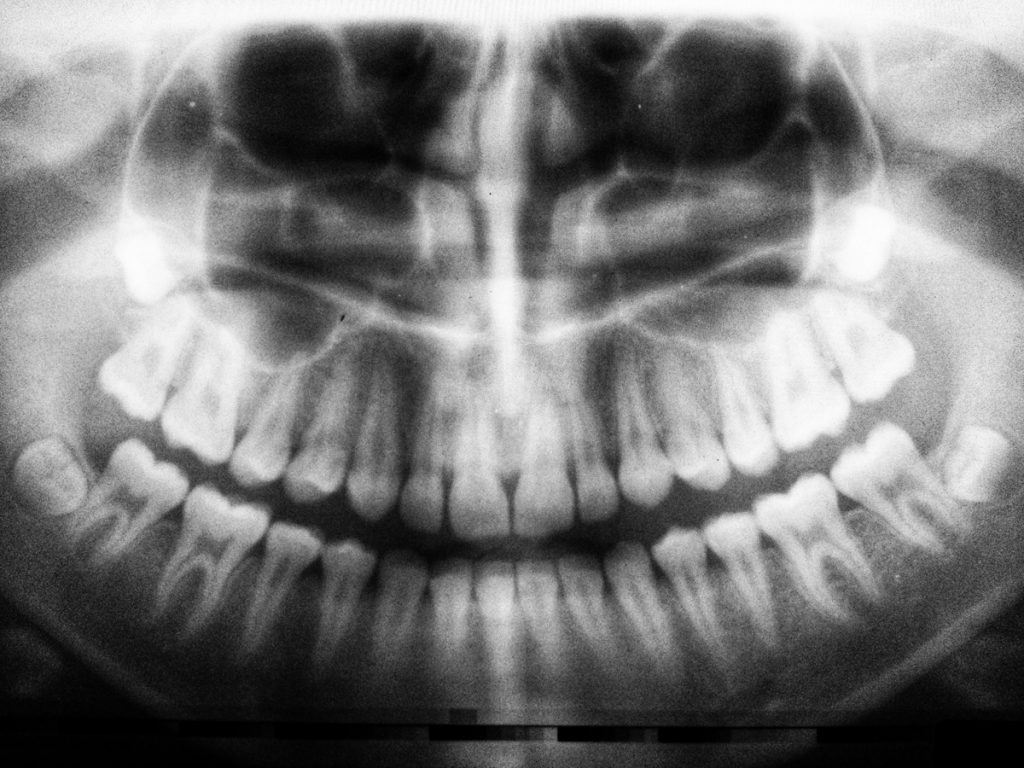

Bruxismo notturno e diurno sintomi e possibili rimedi al digrignamento dei denti Cura dei